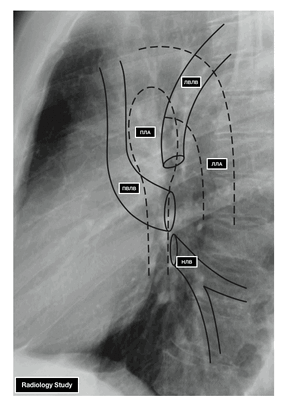

- ЛВЛВ — левая верхняя легочная вена

- ПВЛВ — правая верхняя легочная вена

- НЛВ — нижняя легочная вена

- ПЛА — правая легочная артерия

- ЛЛА — левая легочная артерия

Из двух правых легочных вен больший диаметр имеет верхняя, так как по ней оттекает кровь от двух долей правого легкого (верхней и средней). Из двух левых легочных вен больший диаметр имеет нижняя вена. В воротах правого и левого легких легочные вены занимают их нижнюю часть. В задней верхней части корня правого легкого расположен главный правый бронх, кпереди и книзу от него — правая легочная артерия.

У левого легкого сверху находится легочная артерия, кзади и книзу от нее — левый главный бронх. У правого легкого легочные вены лежат ниже артерии, следуют почти горизонтально и на своем пути к сердцу располагаются позади верхней полой вены, правого предсердия и восходящей части аорты. Обе левые легочные вены, которые несколько короче правых, находятся под левым главным бронхом и направляются к сердцу также в поперечном направлении, кпереди от нисходящей части аорты. Правые и левые легочные вены, прободая перикард, впадают в левое предсердие (их конечные отделы покрыты эпикардом).